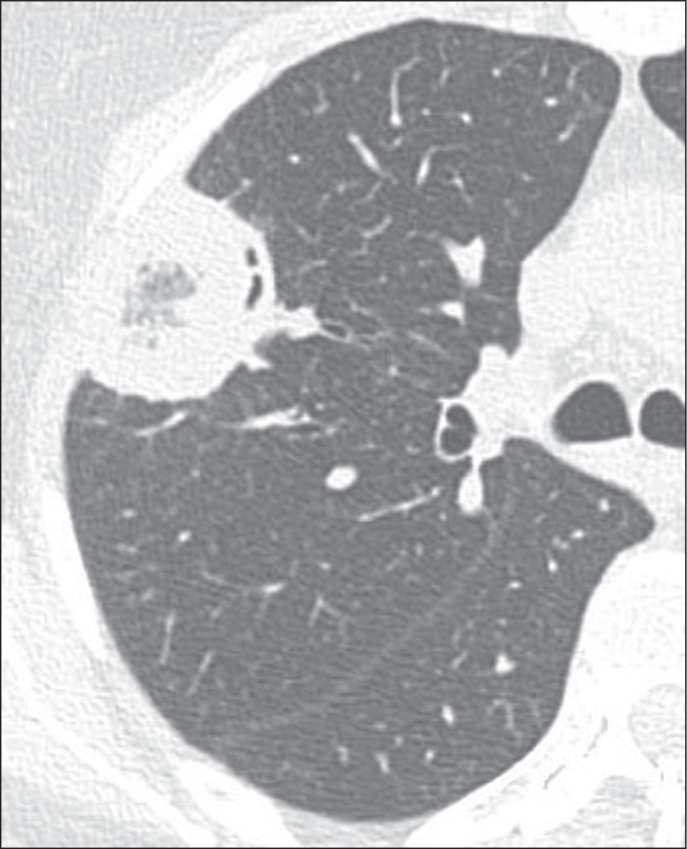

Objective: To characterize the main causes of the reversed halo sign (RHS) on computed tomography (CT) of the chest and its imaging features.

Materials and methods: This was a retrospective study reviewing all chest CT scans for which the report contained the term "reversed halo sign" among those performed between 2015 and 2020 at a tertiary care hospital.

Results: A total of 286 cases were identified, and the corresponding CT images and clinical data were reviewed. In this population, the most common cause of an RHS was pulmonary infarction (in 42%), followed by cryptogenic organizing pneumonia (in 17%) and bacterial pneumonia (in 16%). In addition, the CT characteristics of the RHS were identified in various conditions, such as pulmonary thromboembolism with pulmonary infarction, in which the RHS was typically smooth-walled and solitary with a peripheral distribution.

Conclusion: The RHS can be observed in many contexts, and its CT characteristics, in combination with the clinical picture, can help narrow the differential diagnosis.